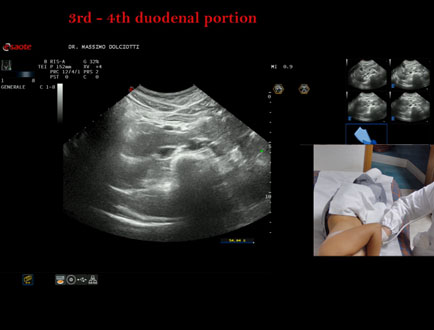

Data inserimento: 19/09/2025

Ecografia del: 10/09/2025

Strumento: Esaote MyLab Eight

Sonda: Convex Multifrequenza 1-8 MHz

Età Paziente: F 24 anni

Motivazione dell'esame:identificazione della terza e quarta porzione duodenale.

Commento all'esame: le immagini ed il video documentano il duodeno ed in particolare la terza e quarta porzione.

Conclusioni: 3° e 4° porzione duodenale (3rd and 4th duodenal portion).

Presentazione: Dr. Massimo Dolciotti - Ancona

Elaborazione digitale: Andrea Dini - Ancona